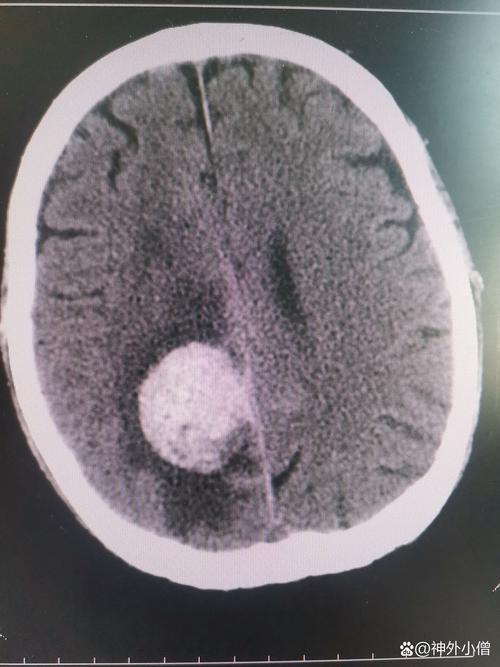

(图片来源网络,侵删)

如何检测和诊断?(在医院进行)

- 影像学检查(金标准):

- 头颅CT扫描: 这是首选和最快的检查,CT可以清晰地显示脑内的出血部位、出血量大小,以及是否破入脑室,在发病几分钟内就能确诊。

- 头颅MRI(磁共振成像): 对于某些不典型的或亚急性期的出血,MRI有更高的敏感性,但通常不如CT快捷。